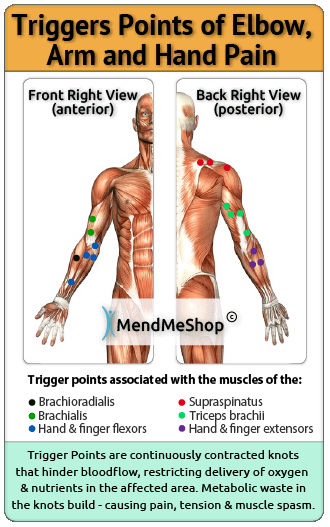

Forearm Muscle Strain

Placements of FSRs on forearm muscles. A Ventral view of right online, Muscles of the Anterior Forearm Superficial View Learn Muscles online, Forearm Anatomy Concise Medical Knowledge online, Right Forearm Anatomy by joechez on DeviantArt online, Forearm Anatomy Concise Medical Knowledge online, Anterior Forearm Basicmedical Key online, Human Anatomy for the Artist The Dorsal Forearm Part 1 online, Anterior Forearm Basicmedical Key online, Right Anterior Forearm Muscles Diagram Quizlet online, Lateral cutaneous nerve of forearm Wikipedia online, Muscles of the Anterior Forearm Deep View Learn Muscles online, Forearm Anatomy Concise Medical Knowledge online, Solved Fig. 13.8 a Pight forearm anterior view b Right online, 7. Muscles of the Forearm and Hand Musculoskeletal Key online, Placements of FSRs on forearm muscles. A Ventral view of right online, Anatomy of the Forearm Trial Exhibits Inc online, Forearm Anatomy Concise Medical Knowledge online, superficial muscles of right forearm Diagram Quizlet online, U.Br.Columbia Drawing Extensor aspect of right forearm English online, Individual Muscles of Forearm Rotators of Radius Anatomy Right online, Dr Shahbaz Ashraf PT Right Anterior Forearm Superficial Muscles online, My study of the right forearm r learnart online, Right and Left Sided Forearm Pain Causes Treatments Buoy online, Right Anterior Forearm Superficial View Diagram Quizlet online, Skin Forearm Right Complete Anatomy online, Forearm Muscle Strain online, 1 Complete view of the forearm. Right forearm. Anterior view online, Persistent Right Forearm Nonunion and Angulation online, X ray Right Forearm AP LAT View Test Price in Delhi Ganesh online, Forearm Anatomy Concise Medical Knowledge online, Forearm pain Causes exercises and stretches online, bones of the right forearm Quiz online, Right Forearm Bones Radius Ulna Anterior View Black White online, U.Br.Columbia Drawing Superficial and deep dissection of right online, Illustration of dissection of the right forearm and elbow online.

Placements of FSRs on forearm muscles. A Ventral view of right online, Muscles of the Anterior Forearm Superficial View Learn Muscles online, Forearm Anatomy Concise Medical Knowledge online, Right Forearm Anatomy by joechez on DeviantArt online, Forearm Anatomy Concise Medical Knowledge online, Anterior Forearm Basicmedical Key online, Human Anatomy for the Artist The Dorsal Forearm Part 1 online, Anterior Forearm Basicmedical Key online, Right Anterior Forearm Muscles Diagram Quizlet online, Lateral cutaneous nerve of forearm Wikipedia online, Muscles of the Anterior Forearm Deep View Learn Muscles online, Forearm Anatomy Concise Medical Knowledge online, Solved Fig. 13.8 a Pight forearm anterior view b Right online, 7. Muscles of the Forearm and Hand Musculoskeletal Key online, Placements of FSRs on forearm muscles. A Ventral view of right online, Anatomy of the Forearm Trial Exhibits Inc online, Forearm Anatomy Concise Medical Knowledge online, superficial muscles of right forearm Diagram Quizlet online, U.Br.Columbia Drawing Extensor aspect of right forearm English online, Individual Muscles of Forearm Rotators of Radius Anatomy Right online, Dr Shahbaz Ashraf PT Right Anterior Forearm Superficial Muscles online, My study of the right forearm r learnart online, Right and Left Sided Forearm Pain Causes Treatments Buoy online, Right Anterior Forearm Superficial View Diagram Quizlet online, Skin Forearm Right Complete Anatomy online, Forearm Muscle Strain online, 1 Complete view of the forearm. Right forearm. Anterior view online, Persistent Right Forearm Nonunion and Angulation online, X ray Right Forearm AP LAT View Test Price in Delhi Ganesh online, Forearm Anatomy Concise Medical Knowledge online, Forearm pain Causes exercises and stretches online, bones of the right forearm Quiz online, Right Forearm Bones Radius Ulna Anterior View Black White online, U.Br.Columbia Drawing Superficial and deep dissection of right online, Illustration of dissection of the right forearm and elbow online.